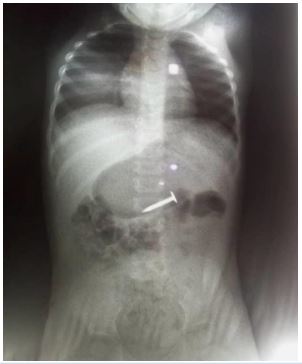

She presented with a plain abdominal radiograph which showed a FB (nail) in the body of the stomach (Figure 1) This was done about 6 hours prior to the presentation at our facility. A repeat radiograph done at the presentation showed the FB (nail) at the region of the terminal ileum (Figure 2). She was commenced on nil per oral, intravenous fluids and monitoring (clinical and radiological). She had two additional plain abdominal radiographs, (Figure 3, 24 hours on admission) and (Figure 4, on day 3). The vital signs remained stable and the abdominal examinations remained equivocal throughout the period of admission. She was discharged following a repeat radiograph which showed no evidence of FB in the GIT.

Figure 1: AP view of plain abdominal radiograph (6 hours prior to presentation).